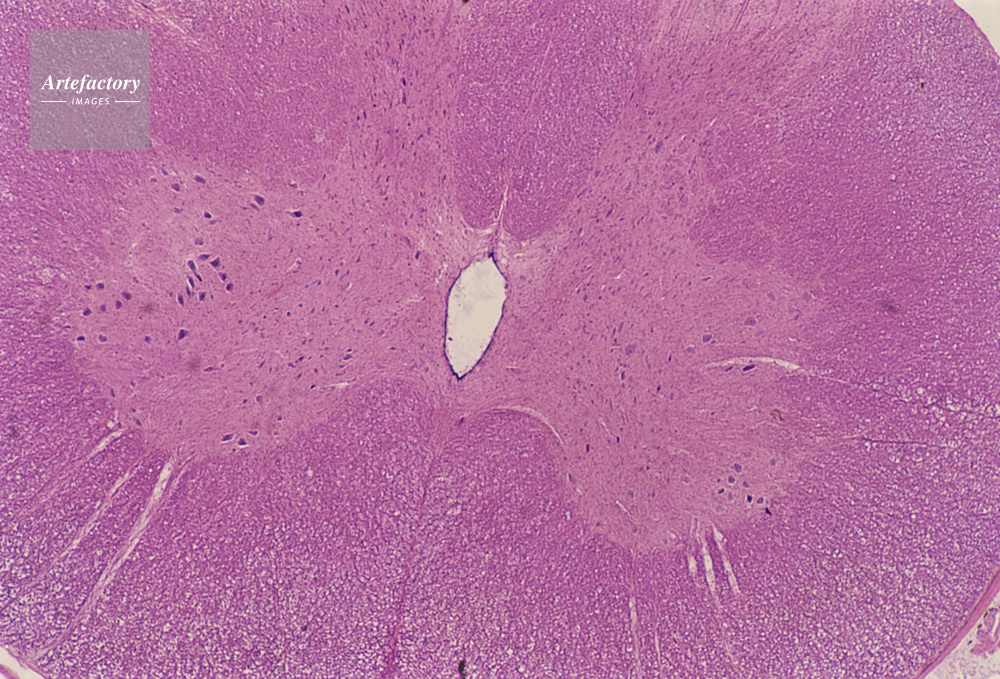

| キャプション | 脊髄,20倍 | 制限事項 | ||